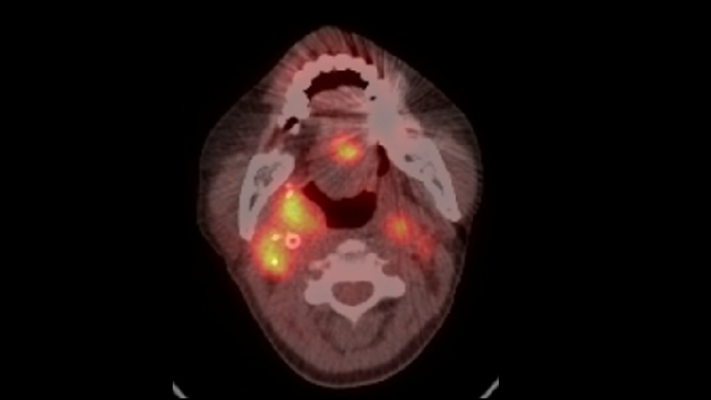

頭頸癌患者的正子攝影,黃色亮部為腫瘤顯影。圖中顯示長期標靶治療帶來的治療壓力,會讓癌細胞提高警覺,接續的免疫療法反而成效不如預期。照:國立陽明交通大學提供